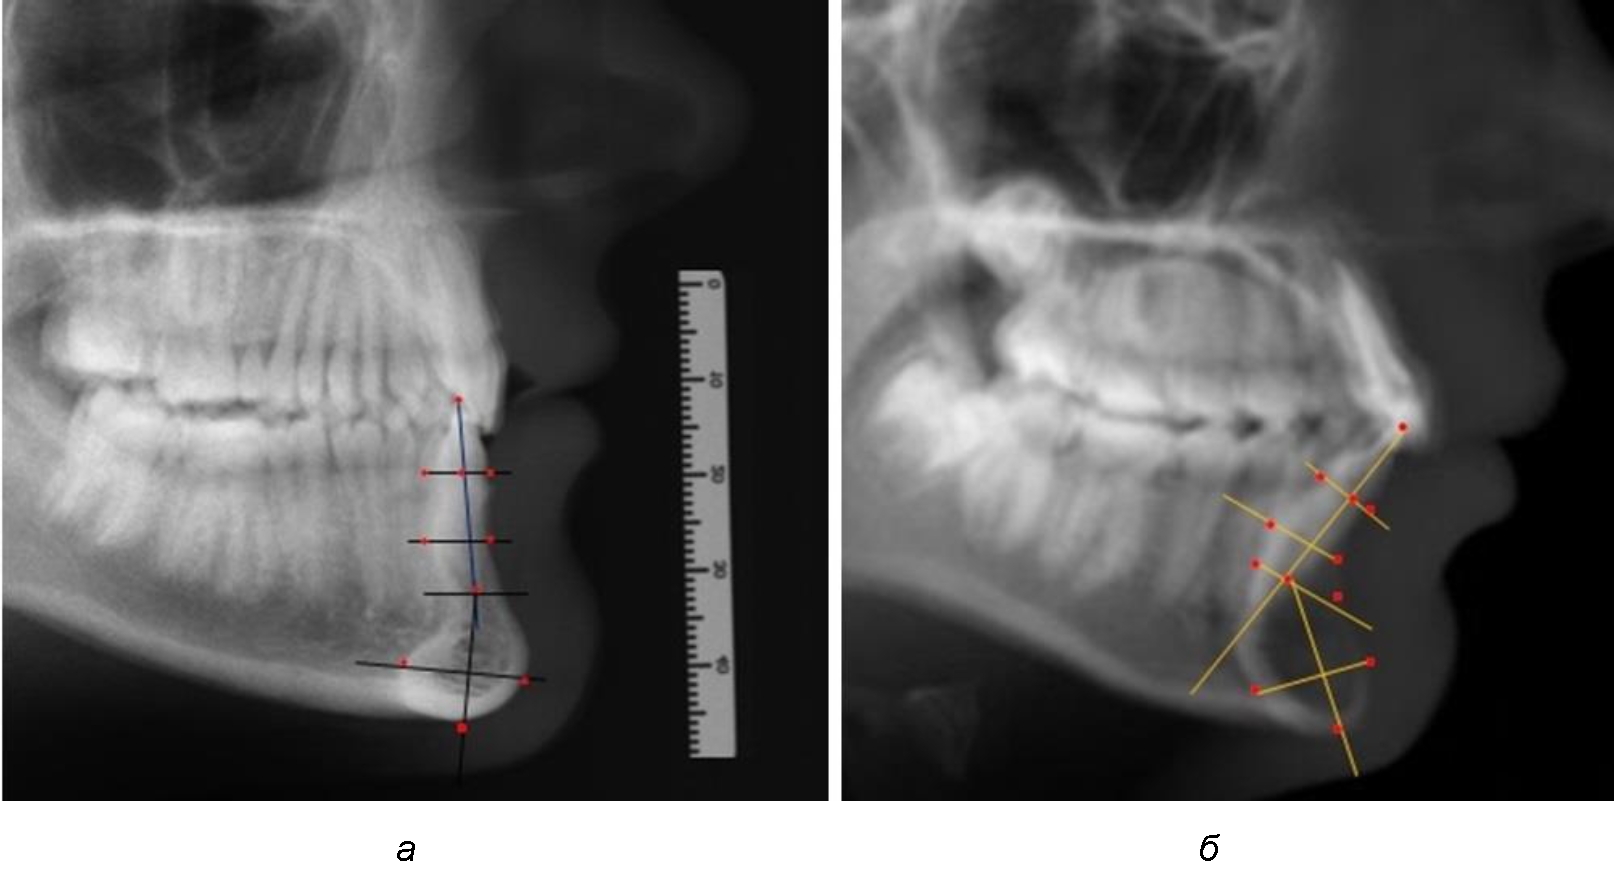

При анализе боковых телерентгенограмм использовали фрагменты гнатической части, на которых оценивали вертикальные и сагиттальные параметры резцового нижнечелюстного сегмента, на который наносили те же ориентиры, что и при анализе нативных препаратов и их рентгенограмм.

При необходимости и/или возможности проведения КЛКТ-исследования проводили анализ с сопоставлением фрагмента, что повышало точность диагностических мероприятий (рис. 2).

Рис. 2. Фрагменты ТРГ с ориентирами для измерения параметров резцового сегмента (а) и с наложением фрагмента КЛКТ (б)

При анализе полученных данных обращает на себя внимание факт того, что из вертикальных параметров зубоальвеолярной части сегмента наиболее вариабельным является размер между апикальными точками Downs и Schwarz (BSM–B), который составлял (6,79 ± 0,54) мм, при величине сигмального отклонения – 2,35. Также большая ошибка репрезентативности и сигмальное отклонение было отмечено при оценки ширины подбородочного выступа. В связи с этим встречались варианты резцовых сегментов нижней челюсти различные как по ширине, так и по высоте, а также по расхождению положения апикальных точек по Downs и Schwarz (рис. 3).

Рис. 3. Варианты среднего (а), широкого (б) и узкого (в) нижнечелюстного резцового сегмента

Варианты резцовых сегментов нижней челюсти различные как по ширине, так и по высоте, а также по расхождению положения апикальных точек по Downs и Schwarz представлены на рис. 4.

Рис. 4. Особенности нижнечелюстного резцового сегмента на ТРГ у людей при среднем (а), широком (б) и узком (в) вариантах